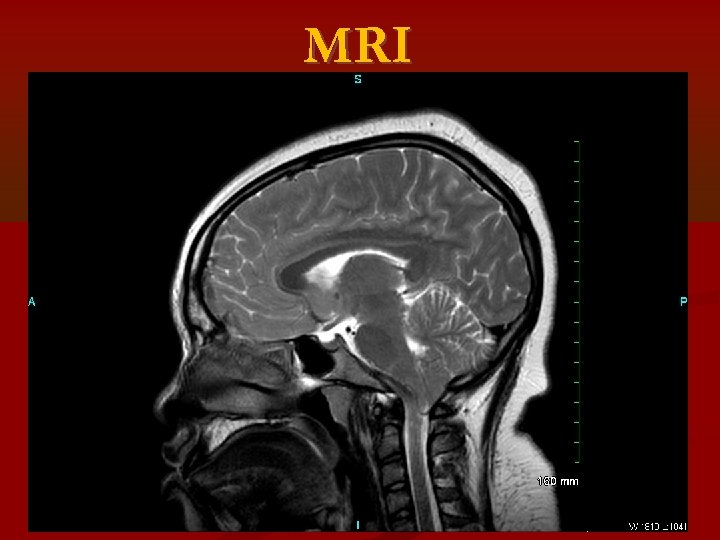

MRI

Idiopathic Intracranial Hypertension (IIH) MRI and MRV to rule out : • Cerebral venous disorders such as cerebral venous obstruction • Systemic or localized extracranial venous obstruction • Dural arteriovenous malformation • Systemic vasculitis • Tumor • Hydrocephalus • Meningeal lesion

Chiari 1 Malformation (CM) : inferior tonsillar displacement (ITD) of 5 mm or more below the Foramen Magnum (FM) Cerebellar Ectopia (CE): ITD more than 2 mm but less than 5 mm below the FM. Retrospective review • 68 patients with Psudotumor Cerebri and available brain MRI • MRIs were analyzed for cerebellar tonsillar position, and results were compared with original reports. Results: By report: 8 (12%) had ITD - 4 had CM, 4 had CE On review: 16 (24%) had ITD- 7 had CM, 9 had. All patients with ITD were female, most were overweight or obese, most had IIH. Primary IIH causing ITD vs primary ITD causing IIH?